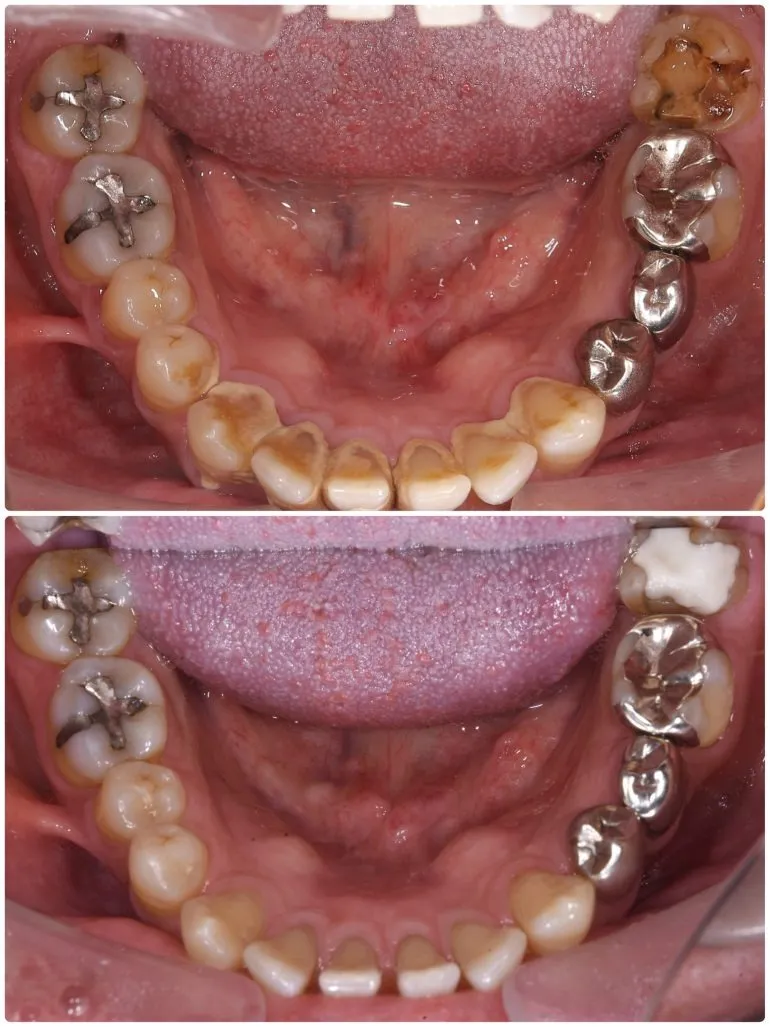

エアフローを使用したクリーニング

治療名

クリーニング

治療説明

治療回数

1回

副作用・リスク

呼吸器系の疾患や、薬剤によるアレルギー、妊娠・授乳期など、お身体の状態によってはエアフローが使用できない場合があります。

料金

保険適用

歯石がこびりついている場合も、保険適用でここまで綺麗になります。

最近歯医者さんに行けていない、または歯医者さんが怖いという方も、ぜひ一度ご相談ください。